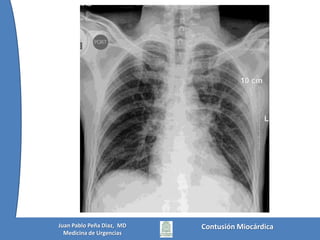

No hay signos de lesión traumática de aortaNo hay signos de contusión pulmonarCorazón y arterias pulmonares normalesNo hay hematoma mediastinalNo hay hemo o neumotóraxContusión MiocárdicaJuan Pablo Peña Diaz,  MDMedicina de Urgencias

Vía Aérea permeableSe colocó O2 bajo Mascarilla de No ReinhalaciónNo hay lesiones visibles en troncoAbdomen blando, doloroso a la palpación del epigastrioPelvis estableSe colocó un bolo de 1.000 cc de SSN y a los 10 min la TA mejoró a 70/50 y luego 110/70No había déficits neurológicos motores ni sensitivos, ni asimetría pupilarE - FAST NegativoEstudios:Contusión MiocárdicaJuan Pablo Peña Diaz,  MDMedicina de Urgencias